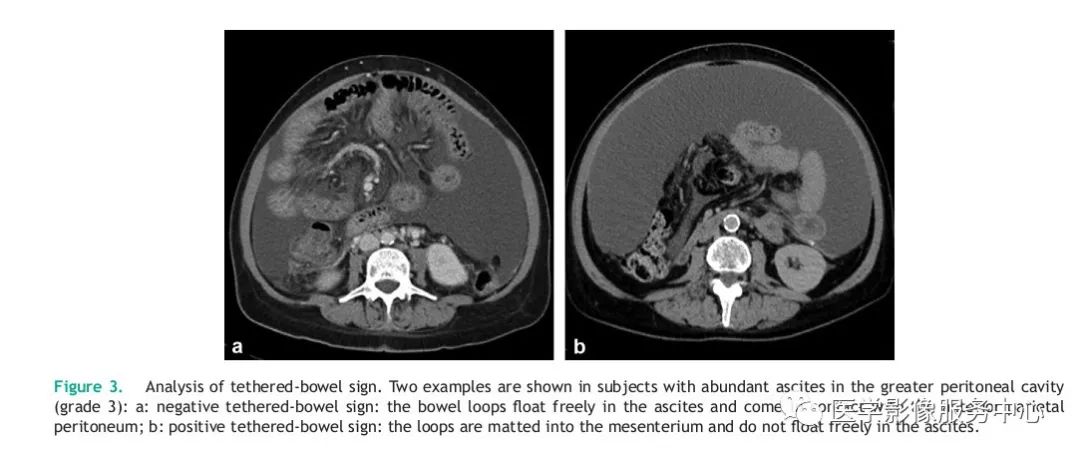

肝硬化腹水与转移性腹水的ct鉴别_医学界-助力医生临床决策和职业成长